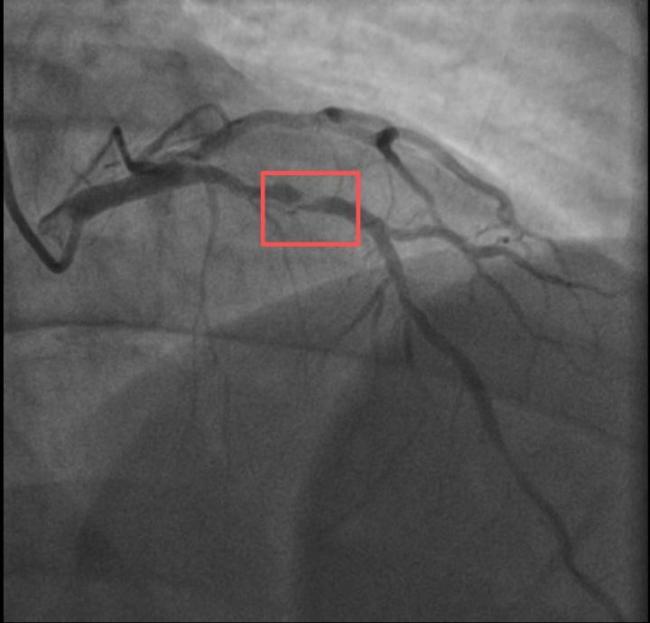

另一位38岁的钱先生也有类似遭遇。钱先生的血糖一直偏高,服药后控制不佳,但年轻的他并没有太在意。周末,他和孩子爬了一座山,隔天就因突发胸骨中段压榨性疼痛被送到了急诊,最后被证实也是心梗——心脏三支主要血管之一回旋支远段次全闭塞。医生介绍,钱先生来院时血糖12.79mmol/L(正常空腹值应该在3.9~6.1mmol/L),甘油三酯也超标。三高是导致动脉粥样硬化的主要危险因素,在冠状动脉粥样硬化早期,血管狭窄可能并不严重,但在运动、情绪激动等情况下,心肌耗氧量增加,可能导致心梗等急性心肌缺血事件。所幸及时治疗,钱先生也转危为安。